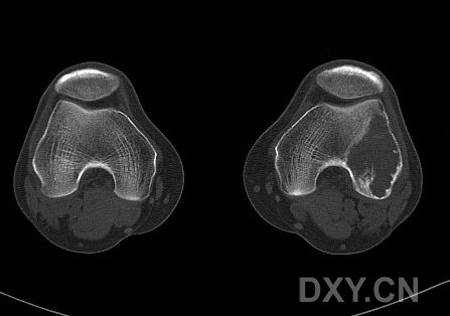

患者,男,38岁,左膝疼痛半月,体检左膝无红肿,无其它既往史

病灶最大径与骨干垂直,病灶呈侵袭性生长,病灶内未见钙化及骨化影,未见骨膜反应,未见软组织肿块,骨壳尚完整.考虑骨巨(良性).

左侧股骨外侧髁囊性低密度灶 考虑 1 骨巨细胞瘤 2 骨囊肿不除外.

骨巨细胞瘤:病变位于骨端,偏心性分布,其内密度均匀,边缘无硬化,无骨膜反应,无软组织肿块,体检左膝无红肿,无其它既往史,及高发年龄

病灶最大径与骨干垂直,病灶呈侵袭性生长,病灶内未见钙化及骨化影,未见骨膜反应,未见软组织肿块,骨壳尚完整.无硬化边.考虑骨巨(良性).

支持骨巨细胞瘤(病灶偏心性生长,无骨化、钙化及骨膜反应,无软组织肿块,内见纤细间隔)。

ct图片太少,x光片示肿瘤呈横向生长,其内可见纤细分隔,符合骨巨的特点,年龄也符合。